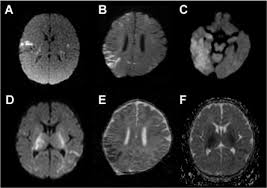

Serology for hsv showed positive hsv (1+2) igg and negative igm. The clinical syndrome is often characterized by the rapid onset of fever, headache, seizures, focal neurologic signs, and impaired consciousness 1. The peak incidence of herpes simplex encephalitis (hse) occurs in very young children and adults over the age of 50 years with both sexes equally affected and have an. Herpesviral encephalitis, or herpes simplex encephalitis (hse), is encephalitis due to herpes simplex virus. There is no particular age, sex, or seasonal predilection. Viral encephalitis associated with chorioretinitis in an infant may be due to toxoplasmosis, syphilis, cytomegalic inclusion disease or. It is estimated to affect at least 1 in 500,000 individuals per year, and some studies suggest an incidence rate of 5.9 cases per 100,000 live births. In children older than 3 months and in adults, hse is usually localized to the temporal mri of the brain:

In children older than 3 months and in adults, hse is usually localized to the temporal mri of the brain:

It is estimated to affect at least 1 in 500,000 individuals per year, and some studies suggest an incidence rate of 5.9 cases per 100,000 live births. Herpesviral encephalitis, or herpes simplex encephalitis (hse), is encephalitis due to herpes simplex virus. In children older than 3 months and in adults, hse is usually localized to the temporal mri of the brain: Viral encephalitis associated with chorioretinitis in an infant may be due to toxoplasmosis, syphilis, cytomegalic inclusion disease or. This is the first study that compared the serum sodium levels. Serology for hsv showed positive hsv (1+2) igg and negative igm. There is no particular age, sex, or seasonal predilection. Imaging in acute herpes simplex.

This is the first study that compared the serum sodium levels hsv encephalitis mri. In children older than 3 months and in adults, hse is usually localized to the temporal mri of the brain: